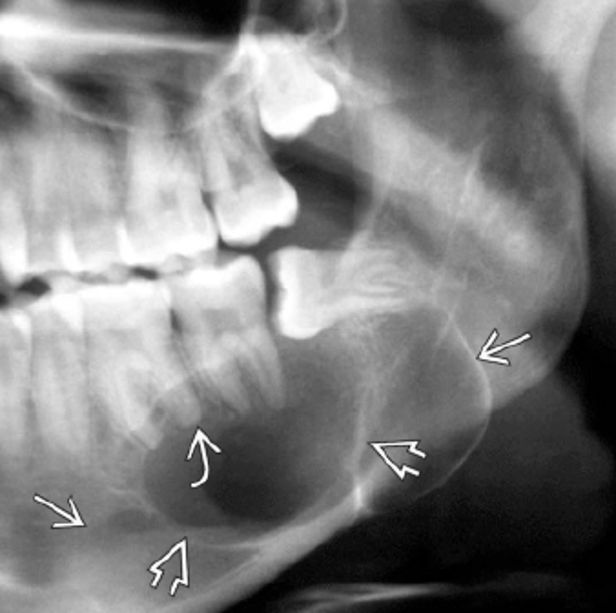

En estas imágenes te mostramos varios casos de la misma patología.

Participa describiendo la patología, dando diagnósticos diferenciales o cualquier comentario que sea útil.

Posterior a sus respuestas estaremos revelando los casos con su información en los comentarios.